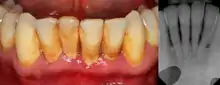

| Gingival enlargement can be a feature in some periodontal diseases. | |

Dental plaque is a microbial biofilm which forms on teeth. This biofilm may calcify and harden, termed calculus (tartar). Plaque tends to build up around the gingival margin (the gumline) and in gingival crevices or periodontal pocket (below the gumline). The release of waste products from the bacteria living in the biofilm causes an inflammatory response in the gums which become red and swollen, bleeding easily when disturbed. This is termed plaque-induced gingivitis and represents the most common form of gingival disease.[5] This inflammatory response in the host can be strongly influenced by many factors such as hormonal fluctuations, drugs, systemic diseases, and malnutrition;[4] which may allow further subdivision of plaque-induced gingivitis (see table).

The defining feature of periodontitis is connective tissue attachment loss which may manifest as deepening of periodontal pockets, gingival recession, or both. This loss of support for the teeth is essentially irreversible damage. Chronic periodontitis is generally slow to moderate in terms of disease progression, although short bursts of increased tissue destruction may occur. Ultimately, tooth loss may occur if the condition is not halted. It is termed localized when less than 30% of sites around teeth are involved, and generalised when more than 30% are involved. clinical attachment loss can be used to determine the severity of the condition, where 1–2mm is slight, 3–4mm is moderate and more than 5mm is severe.[5]